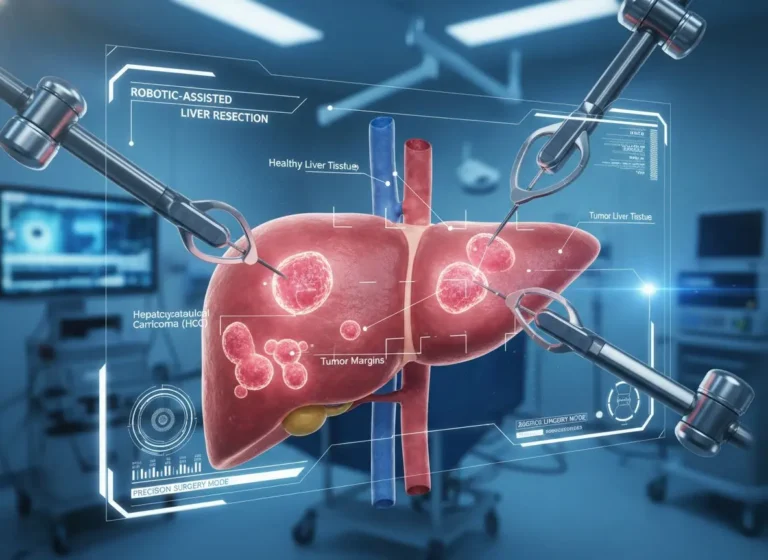

This is the spark that ignites ideas and fuels transformation; from here, the path forward becomes clear Liver Tumour Surgery in Mira…

If you or someone close to you has recently been diagnosed with liver cancer, you’re probably feeling overwhelmed, scared, and unsure about…